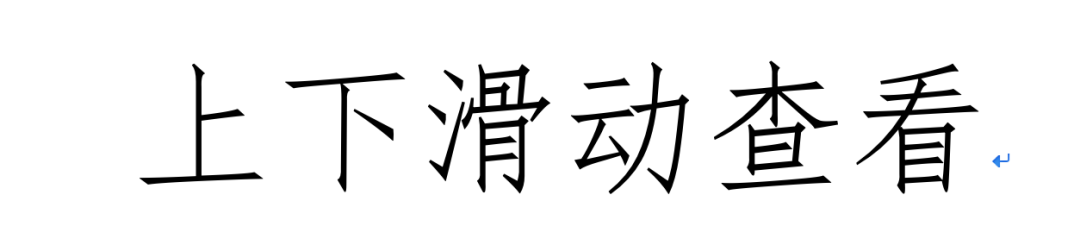

距腓前韧带距骨侧和腓骨侧双束断裂

踝关节严重不稳